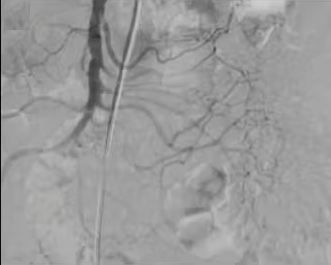

诊断和下消化道出血的栓塞需要高质量的血管造影图像显示清晰的解剖轮廓,做到 | ||||||||||||||||||||||||||||||||||||||||||||||||||||||

| 出血点险些出覆盖范围(最下方) | 右结肠动脉出自腹腔动脉 |

投照没有足够低的中心 Failing to Center Low Enough

造影剂外溢发现 0.5 mL/min

DIRECT SIGNS - EXTRAVAZATION OF CONTRAST MEDIA

INDIRECT SIGNS 一 PSA, ARTERIAL WALL IRREGULARITIES